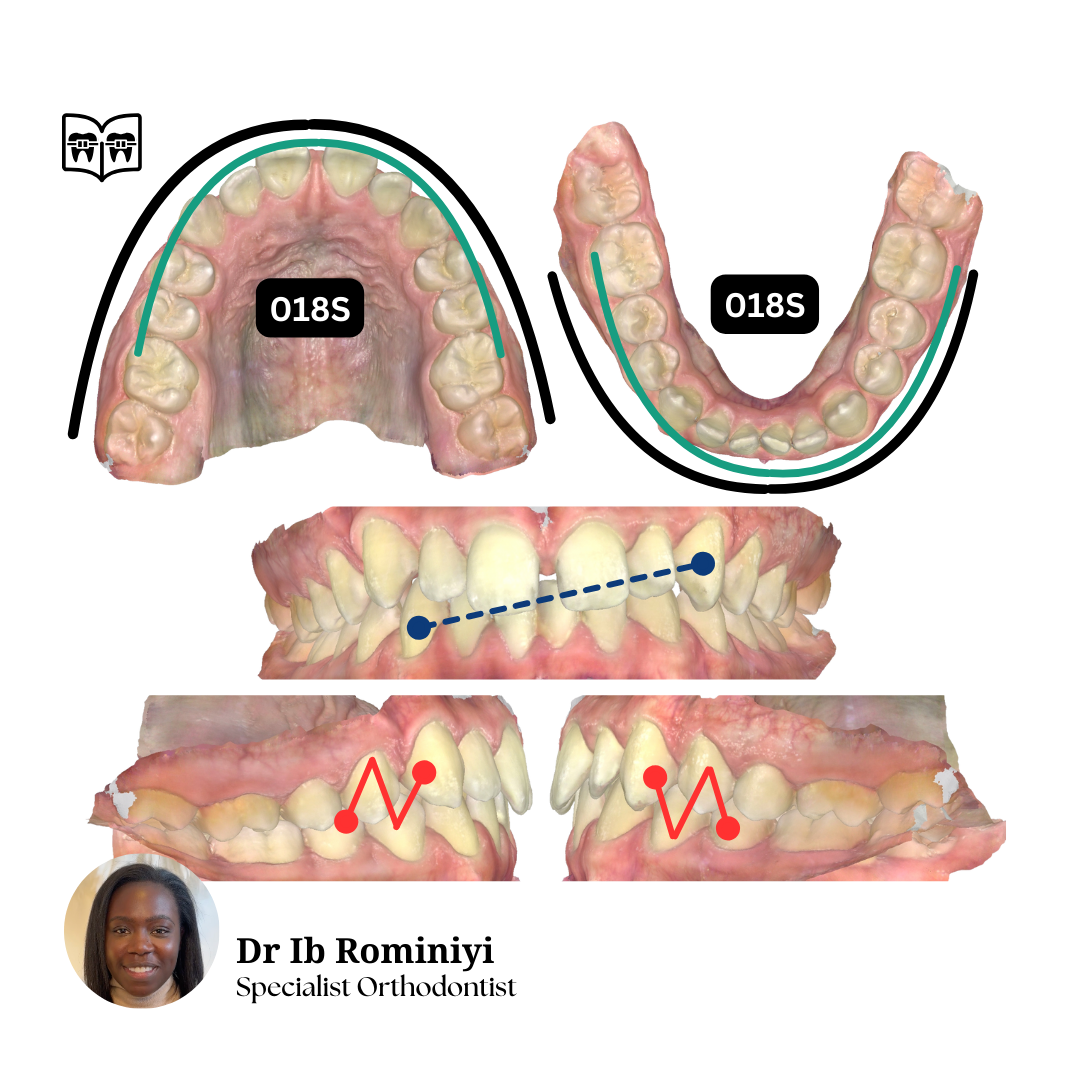

Dentist's Question: I'm currently in upper 19x25N, lower 18x25S and the lateral open bites and centrelines are getting worse.

How would you improve the bite?

What mechanics & archwires would you use from here?